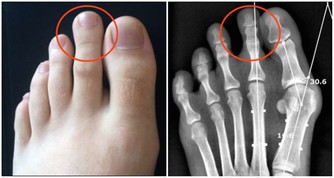

3,眼睛模糊;指甲表面有凸起的棱線,或者凹陷;肝主目,也主筋,如果肝血(肝血)不足,則不能視,手握無力;指(趾)甲表面就不光滑。